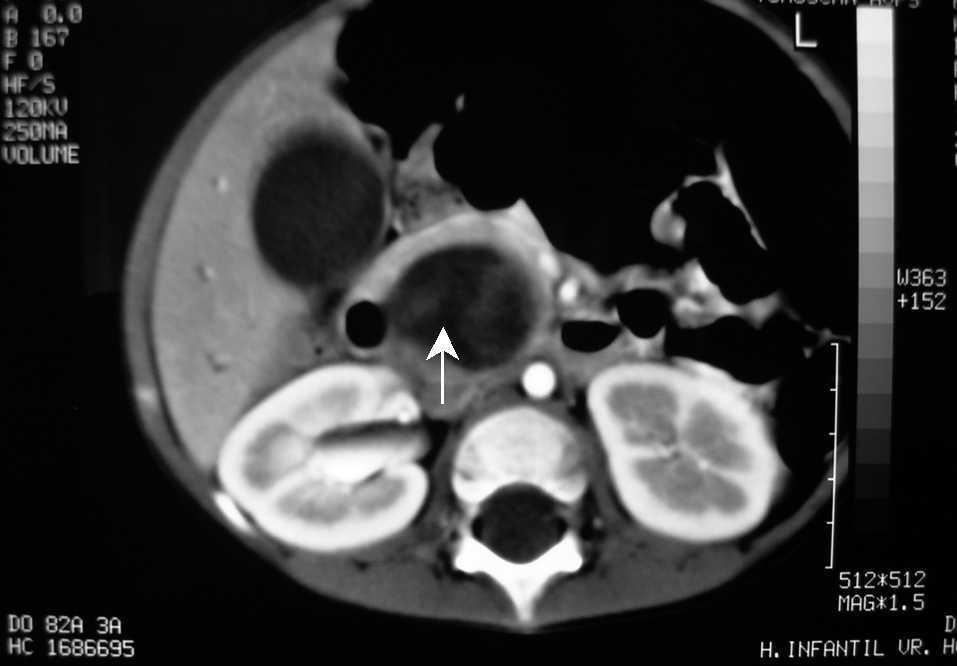

Se realiza una tomografía computarizada (TC) de abdomen que pone de manifiesto una dilatación de la vía biliar intrahepática, visualizándose una imagen redondeada de mayor densidad que la vesícula biliar que desplaza la arteria hepática (fig. 1). La colangiorresonancia realizada mostró una dilatación fusiforme del hepatocolédoco, visualizándose un defecto de repleción intraluminal en el colédoco distal, que ocasiona obstrucción y dilatación retrógrada de la vía biliar (fig. 2).

Figura 1.TC de abdomen: dilatación de la vía biliar intrahepática, visualizándose una imagen redondeada de mayor densidad que la vesícula biliar que desplaza la arteria hepática.